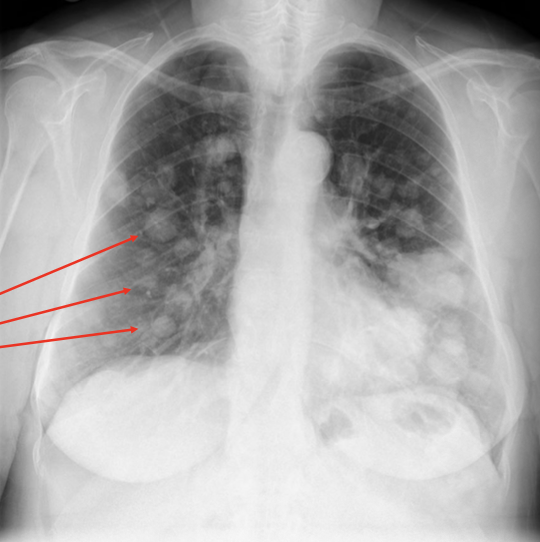

Pathology?

Pneumonia (alveolar air replaced with fluid, obscures lung markings)